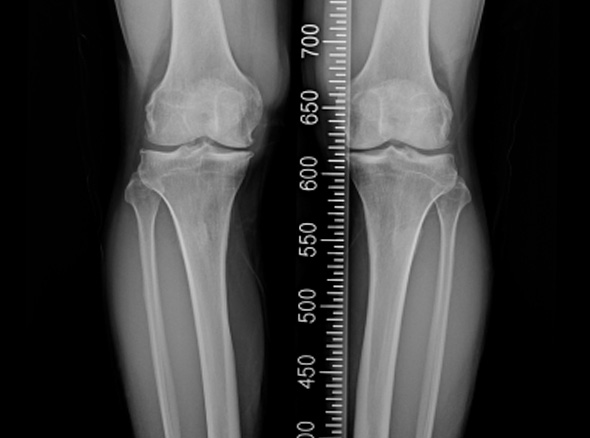

한국인의 대부분에게서 무릎 내측에 무릎 관절염이 발생됩니다.

관절내시경을 이용하여 연골재생이나 연골판에 필요한 치료를 시행한 후 경골(무릎 아래 뼈)의 근위부의

계획한 위치까지 절골을 시행한 후 뼈의 탄성을 이용하여 벌립니다. 그리고 금속판과 나사로 고정하여

수술 전 계획했던 X자형 또는 1자형 다리를 만들고 빈 공간에 뼈를 이식하여 골유합을 유도합니다.